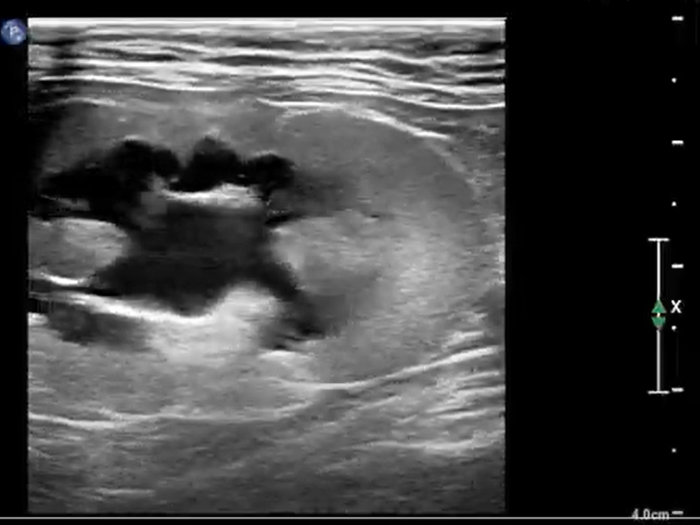

Desafío Veterinario: Citología

Llega a consulta; una perra chihuahua de 12 años edad, presenta una masa de 3 cm en la región inguinal, con características irregulares, ulceradas y supurativas. La masa ha crecido rápidamente en las últimas dos semanas. A pesar de que sus constantes vitales y análisis de laboratorio son normales, se recomienda realizar un estudio citológico.